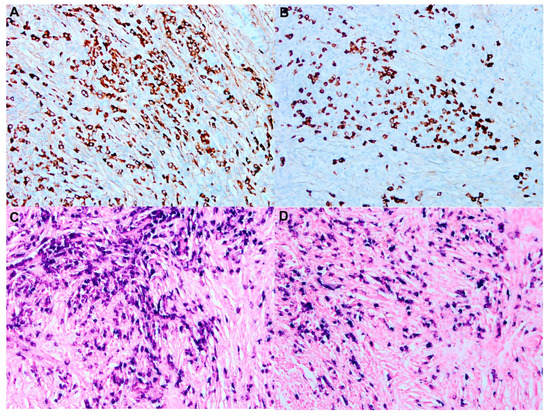

7. Histopathology and Immunochemistry

- Garces, S.; Medeiros, L.J.; Marques-Piubelli, M.L.; Coelho Siqueira, S.A.; Miranda, R.N.; Cuglievan, B.; Sriganeshan, V.; Medina, A.M.; Garces, J.C.; Saluja, K.; et al. Cyclin D1 expression in Rosai-Dorfman disease: A near-constant finding that is not invariably associated with mitogen-activated protein kinase/extracellular signal-regulated kinase pathway activation. Hum. Pathol. 2022, 121, 36–45. [Google Scholar] [CrossRef]